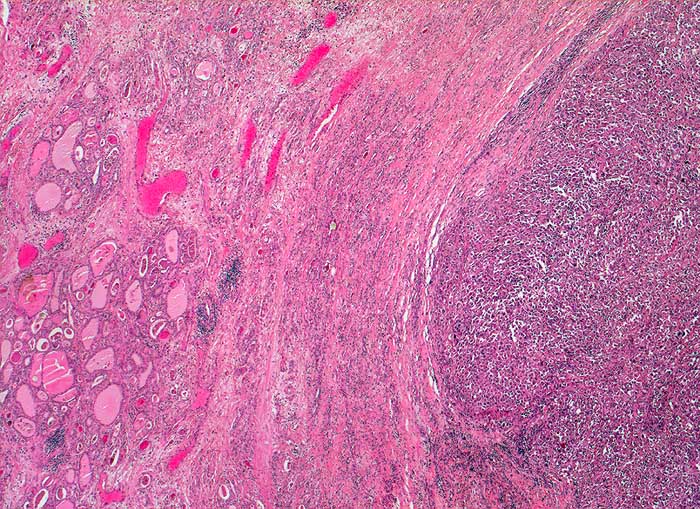

PathoPic – image database / PathoPic ID 5460 - Anaplastisches Schilddrüsenkarzinom

Anaplastisches Schilddrüsenkarzinom

Zwischen Schilddrüsenparenchym und solidem Tumorknoten liegt eine dicke bindegewebige Kapsel. Bereits in dieser Vergrösserung ist erkennbar, dass der Tumor weder follikuläre noch papilläre Strukturen enthält.

Strumaknoten links mit Einengung der Trachea